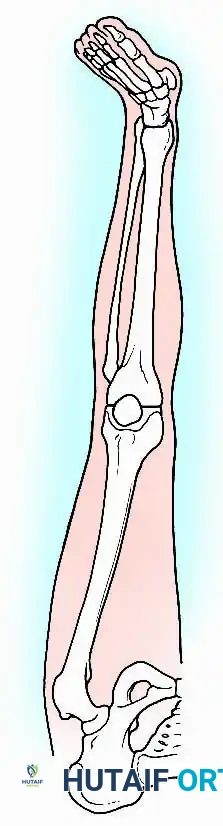

Optimal Positioning for Fusion

Achieving the correct multiplanar alignment is critical for maximizing gait efficiency and minimizing adjacent joint degeneration (particularly in the ipsilateral hip and lumbar spine).

- Flexion: 0 to 15 degrees. While Charnley historically advocated for complete extension for cosmetic reasons, a slight flexion angle (10-15 degrees) significantly aids in clearing the foot during the swing phase of gait and provides a more functional posture for sitting.

- Valgus: 5 to 8 degrees. This restores the normal mechanical axis of the lower extremity, ensuring physiological load distribution through the hip and ankle.

- Rotation: 10 degrees of external rotation, matching the normal foot progression angle.